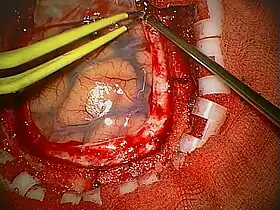

A craniotomy is a surgical operation in which a bone flap is temporarily removed from the skull to access the brain. Craniotomies are often critical operations, performed on patients who are suffering from brain lesions, such as tumors, blood clots, removal of foreign bodies such as bullets, or traumatic brain injury (TBI), and can also allow doctors to surgically implant devices, such as deep brain stimulators for the treatment of Parkinson's disease, epilepsy, and cerebellar tremor. The procedure is also used in epilepsy surgery to remove the parts of the brain that are causing epilepsy.

Human craniotomy is usually performed under general anesthesia but can be also done with the patient awake using a local anaesthetic; the procedure, typically, does not involve significant discomfort for the patient. In general, a craniotomy will be preceded by an MRI scan which provides an image of the brain that the surgeon uses to plan the precise location for bone removal and the appropriate angle of access to the relevant brain areas. The amount of skull that needs to be removed depends on the type of surgery being performed. The bone flap is mostly removed with the help of a cranial drill and a craniotome, then replaced using titanium plates and screws or another form of fixation (wire, suture, etc.) after completion of the surgical procedure. In the event the host bone does not accept its replacement, an artificial piece of skull, often made of PEEK, is substituted. (The PEEK appliance is routinely modeled by a CNC machine capable of accepting a high resolution MRI computer file in order to provide a very close fit, in an effort to minimize fitment issues, and therefore minimizing the duration of the cranial surgery.)